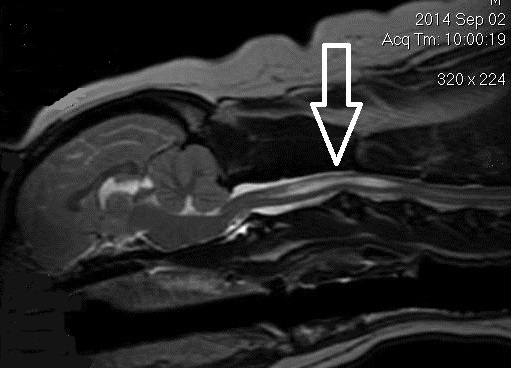

(See above a magnetic resonance imaging [MRI] scan of a

cavalier's brain and spinal cord, with the arrow

pointing to a syrinx [the

elongated white area] within the spinal cord. The blue and gray diagram

at right -- prepared by Dr. Rusbridge -- shows the location of the syrinx

within the spinal cord. In the images of a cavalier

below, the red arrow points from a syrinx to a cross-section of the spine at

that point. This image is Figure 3 from this

November 2018 article.)